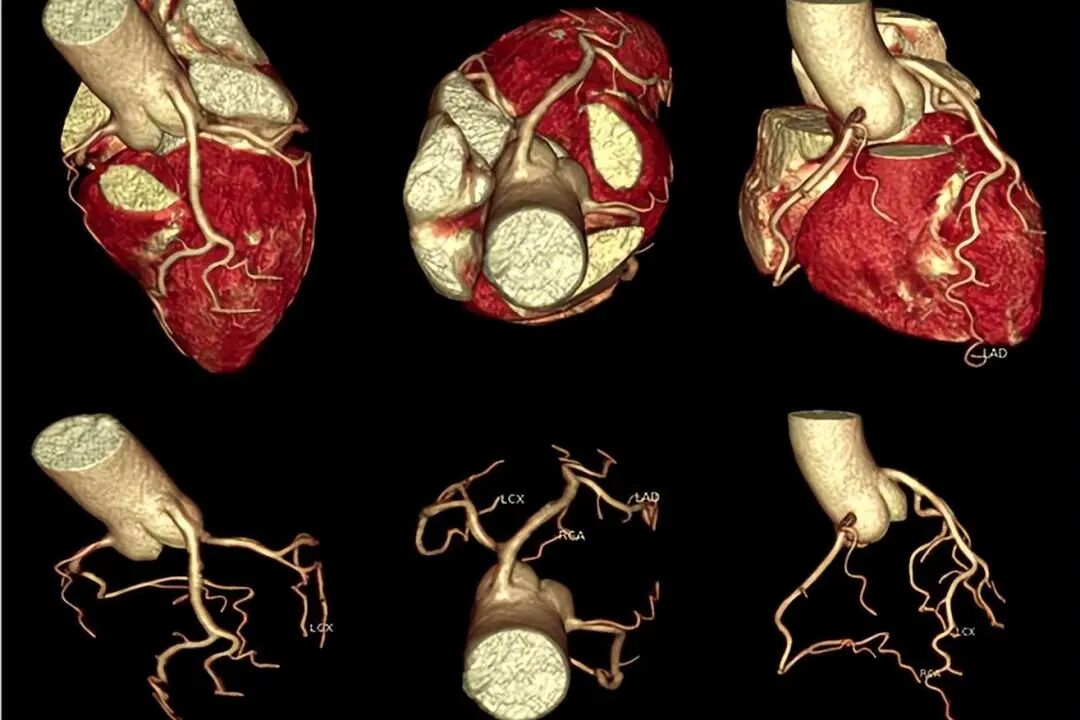

别被“CT”吓到,其实它比很多检查都简单。一个无创、无痛的高分辨率成像技术,能立体还原你冠状动脉的全貌。

做完后,医生可以直观看到血管内有没有斑块,斑块大小、位置、是否钙化,以及有没有引发血管狭窄。

冠脉CT就是“拍”出看得见的实景图,甚至比开刀看病灶还准。据《中华心血管病杂志》统计,即使是早期无症状的患者,有斑块者3年内发生心脑血管事件的风险,是无斑块者的10倍以上。

我院新进的中国首台16cm全景多模态CT,专为心脏检查而生。它拥有0.17毫米的超高分辨率,配合人工智能(AI)辅助分析系统,能够精准识别毫米级的微小斑块,并自动分析斑块性质、血管狭窄程度。无论是常规体检,还是复杂的支架术后复查,这台设备都能提供高清、可靠的诊断依据,是各类高端体检人群的首选检查。